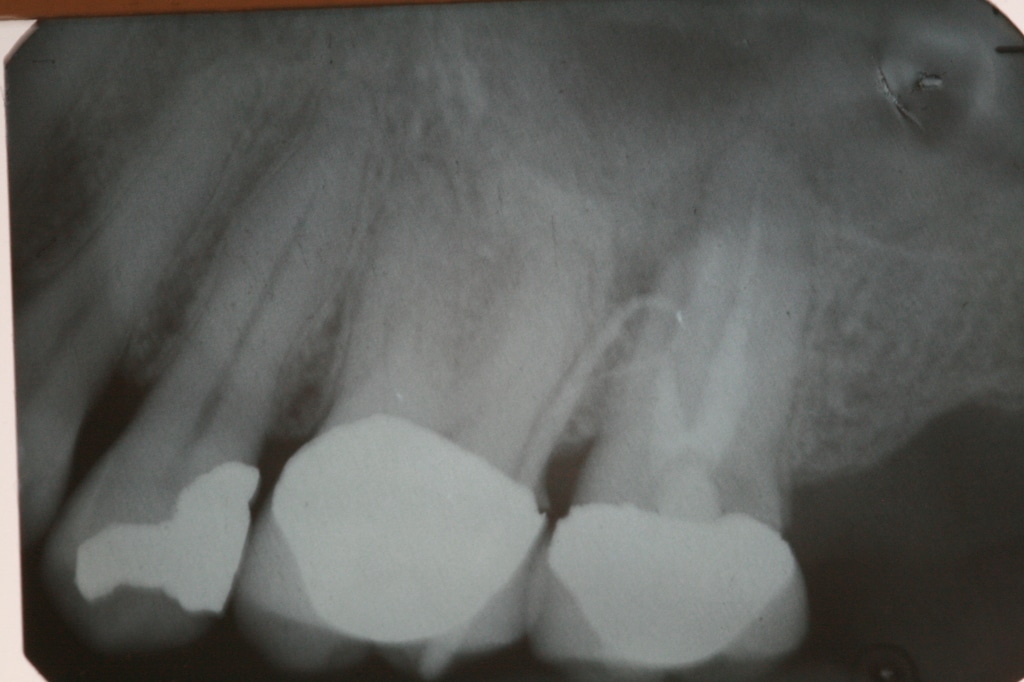

Figure 1 from Threeyear followup Healing of a large periapical Failed Root Canal Fistula | what to look for. did your root canal fail? — common signs and symptoms of root canal failure. Learn about the signs, causes, and treatment options for a failed root canal, and get back on track to a healthy smile. — learning the signs and symptoms of a failed root canal can help you get treatment. Failed Root Canal Fistula.

Failed endodontic treatments. Above, resorption associated with 46 and Failed Root Canal Fistula — what happens if a root canal fails? — learning the signs and symptoms of a failed root canal can help you get treatment and successfully save your natural tooth. Learn about the signs, causes, and treatment options for a failed root canal, and get back on track to a healthy smile. Your nyc endodontist has several options,. Failed Root Canal Fistula.